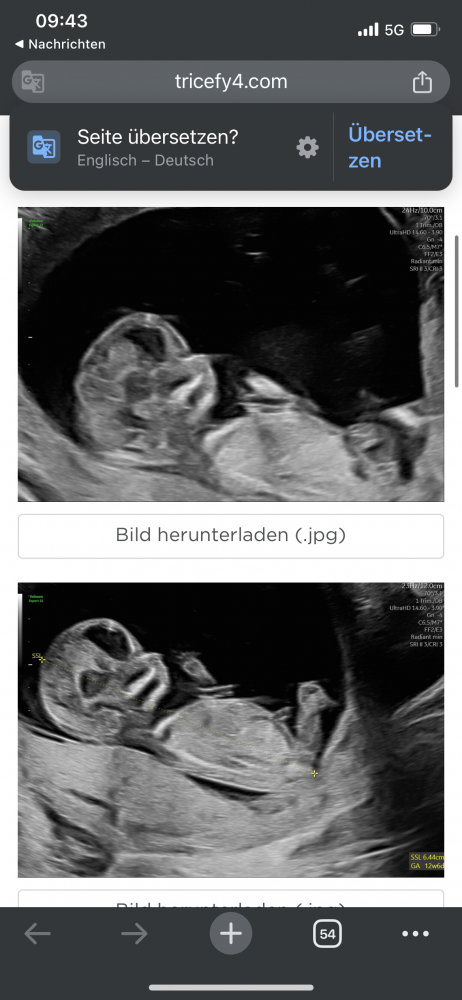

War heute beim US (12+5) und bin mir nicht sicher: Ist das überhaupt der NUB und wenn ja, was würdet ihr sagen, was es wird?

Danke schon mal im Voraus 😊

Hallo zusammen👋🏻